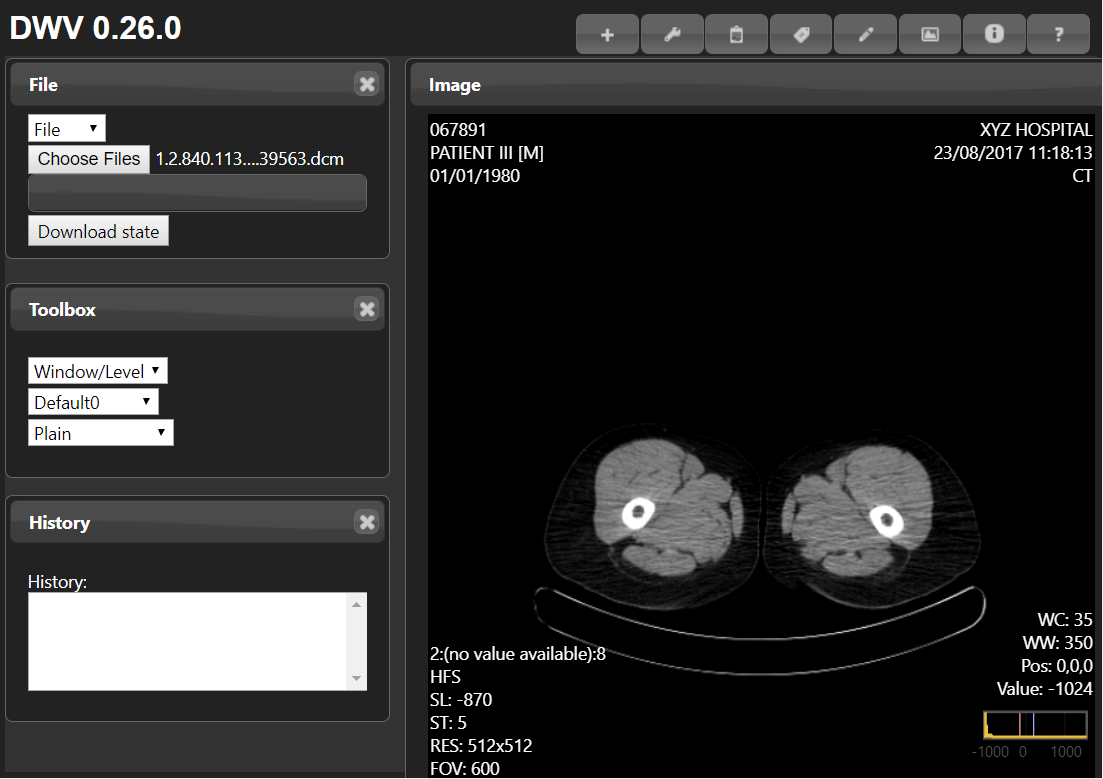

This is a browser-based DICOM viewer, which means it cannot be downloaded, but can be accessed through any device with an internet browser—your laptop, phone, tablet, or even smart televisions. Only basic manipulation of the image (drag, zoom, contrast) can be done, and as this is view-only, export is not possible. The application requires some technical skill to navigate around, but videos and support is offered.